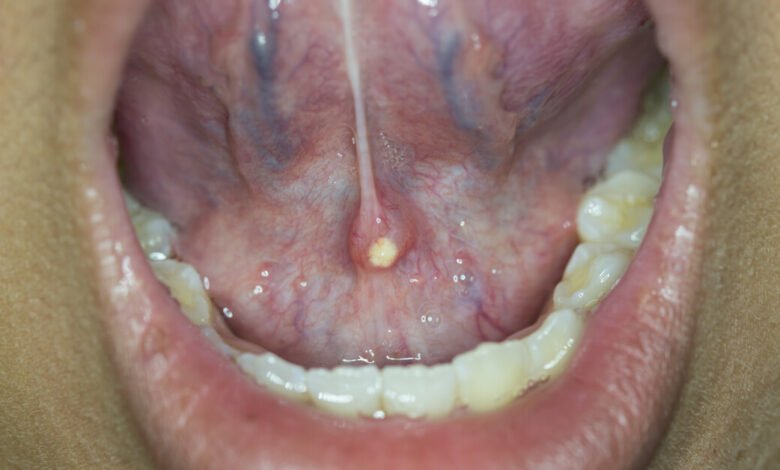

أسباب الإصابة بحبة اللسان: تُعتبر حبة اللسان عبارة عن نمو شبيه بالحليمات الموجودة في الفم، بحيث تكون عبارة عن نمو صغير يسبب المزعة والألم الشديد في اللسان والتي لا تسبب أي شيء خطير. ويمكن أن يصيب حبة اللسان أي شخص في أي وقت، ولكن يبدو من المرجّح أن هذه الحالة تفتقر إلى نظرية واضحة حول الأسباب المؤدية إلى حدوثها.

تُعَد حبة اللسان ظاهرة شائعة ، وتوجد العديد من الأسباب المحتملة التي قد تؤدي إلى الإصابة بها . على سبيل المثال:

- التهابات الفم: إذا كنت تعاني من التهابات اللثة ، أو العقدية الموجودة في الفم ، فقد تكون معرضًا للإصابة بحبة اللسان.

- تغييرات هرمونية: تُشير الأبحاث إلى أن حبة اللسان يحدث بشكل أكبر للنساء خلال فترات التغيير الهرموني ، مثل الحمل أو سن اليأس.

- العوامل الغذائية: يمكن أن يسبب الطعام المحفزات ، مثل المشروبات الغازية ، أو تناول الأطعمة الملتهبة، حدوث حبة اللسان.

- مرض الشقيقة: يمكن أن يزيد مرض الشقيقة خطر الإصابة بحبة اللسان.

- قلة التحمل النفسي: يظهر حبة اللسان في بعض الأحيان في الأشخاص الذين يعانون من الإجهاد النفسي.